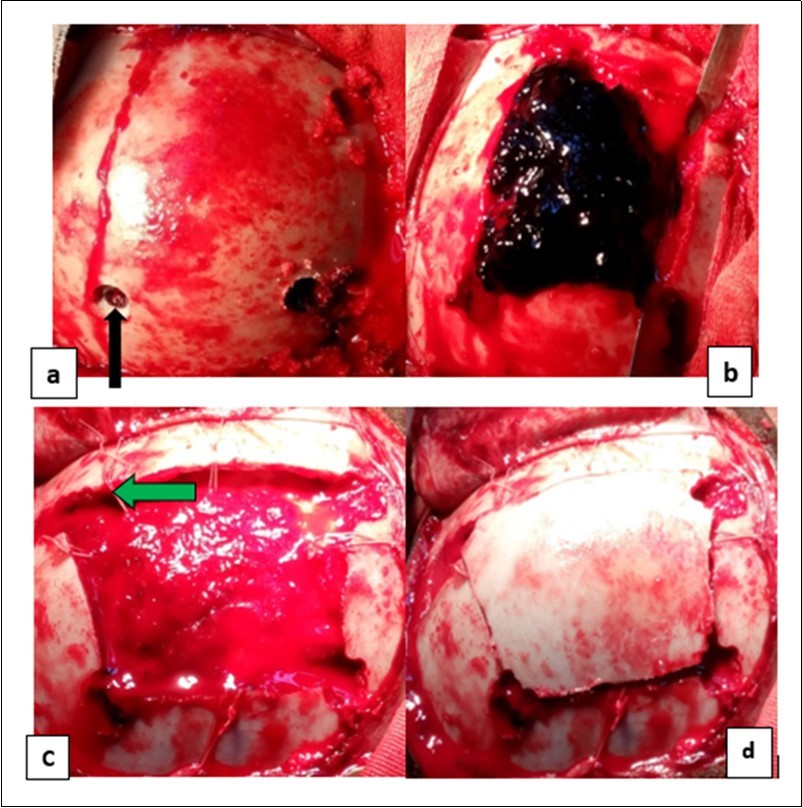

From the point of view of care, two (n=2) (10.52%) children received medical treatment compared to 17 (89.48%) children who received medical-surgical treatment. Neurosurgical treatment consisted of evacuation of the extra dural hematoma. This involved making a skin incision, trepanation (Figure 3 a), a preserved cranial bone flap, evacuation of the extra-dural haematoma (Figure 3 b), haemostasis either of the bone using bone wax or venous or arterial haemostasis by bipolar coagulation as appropriate, suspension of the dura mater (Figure 3 c), replacement of the bone flap (Figure 3 d) and finally suturing of the scalp in two planes. Figure 1, Figure 2, Figure 3.

Figure 3.Operating times for an extra dural hematoma: a) making a cranial bone flap with three drill holes (the black arrows); b) extra dural hematoma after craniotomy (by the blue arrows); c) image showing the dura mater then suspension of the dura mater (the green arrows) and d) image after handing over the bone flap.